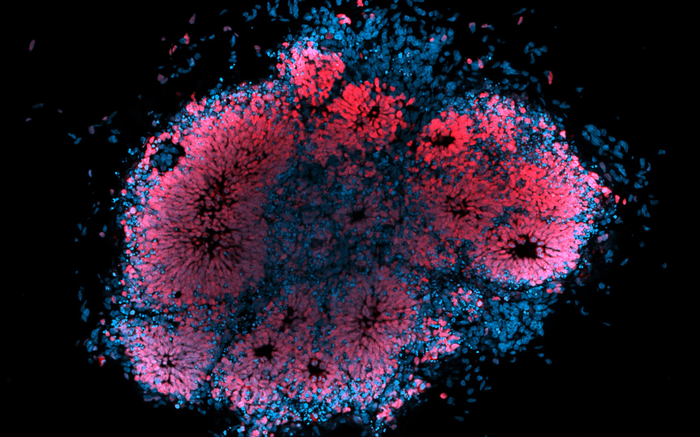

IMAGE: MICROSCOPIC IMAGE OF HUMAN BRAIN ORGANOID INFECTED WITH ZIKA VIRUS. view more

CREDIT: DR JULIO AGUADO (AIBN, UQ)

A University of Queensland-led project has used a ‘brain in a dish’ to study the effects of the Zika virus, taking research a step closer towards developing drugs to combat the infection.

“It’s a little like something out of a science fiction movie – we’re growing an artificial and microscopic human brain in a petri dish and testing the effect of the virus on its cells,” Dr Slonchak said.

“Stem cells self-organise into organ-like structures, or organoids, and in this case they have the structure and tissue architecture of the developing human brain.

“Our study shows the role of viral noncoding RNA in transplacental infection in pregnant mice and in cell death in human brain organoids.